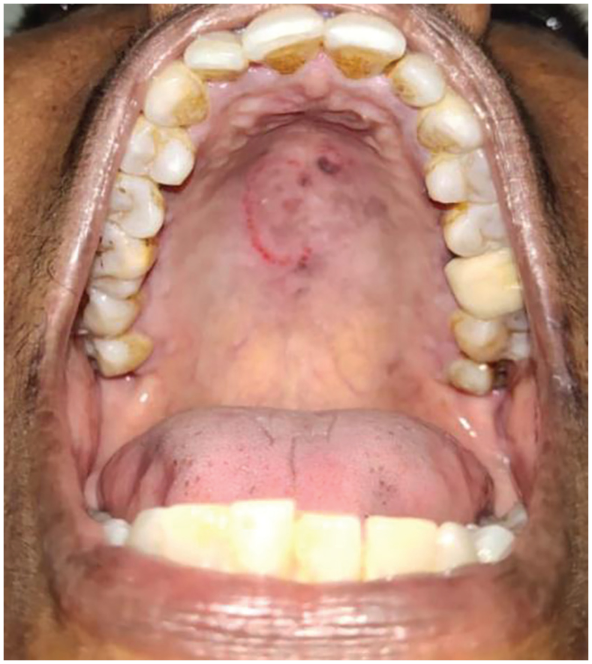

A 57-year-old female patient visited the dental office with the chief complaint of pain in the right mandibular molar region. The pain was a dull ache and intermittent in nature. Upon intra-oral examination, caries in tooth 36 was noted. It demonstrated mild tenderness on percussion. A radiographic image revealed pulpal involvement of the carious lesion in tooth 36. She was recommended for endodontic. With mild calculus deposits and stains, she maintained a fair oral hygiene. The patient was known to be diabetic, hypertensive, and under medication, but did not follow a regular check-up schedule. During the intra-oral soft tissue examination, a round area of erythematous petechiae with a clear center of about 3 cm maximum diameter was identified on her palate (Figure 1 [Fig. 1]).

Figure 1: Erythematous palatal petechiae with a clear center of about 3 cm

The patient was unaware of the lesion and she was asymptomatic at the time of her visit. Nevertheless, we performed a more personal anamnesis, finding that her sexual practice of fellatio, with the last instance of 3 days prior to her dental visit, was reason for the development of the palatal petechiae. Serological laboratory tests for human immunodeficiency virus (HIV) and venereal disease were negative. The etiology of her palatal lesion was explained to the patient, and she was advised to maintain good oral hygiene.